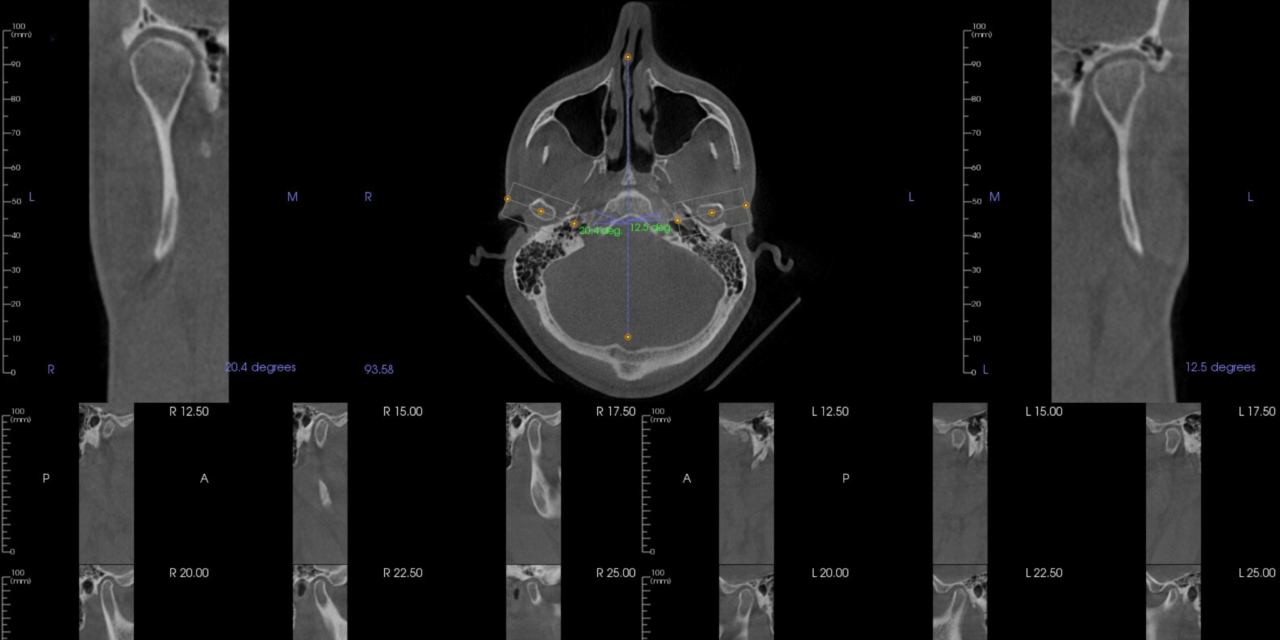

Tmj Disorder Understanding Jaw Pain And Headaches Rudnick Dentistry As a las vegas institute fellow, he has completed the most advanced training for cosmetic and restorative dentistry, which includes complex full mouth restorations, occlusion, dental implants, and sleep apnea tmj treatments. Tmj disorder affects your jaw joint and muscles, causing pain and movement issues when your jaw opens. tmj disorders affect the joints in your jaw and the muscles around them. the medical term is temporomandibular joint dysfunction (tmd), but many people call it tmj.

Understanding Jaw Pain Tmj Disorder And How To Find Relief Maryland Temporomandibular joint syndrome (tmj) symptoms include a popping or clicking of the jaw, jaw and or ear pain, tinnitus, and headaches. learn how to get relief for your tmj pain. Tmj disorders diagnosis your healthcare professional will likely discuss your symptoms and study your jaw by: listening to and feeling your jaw when you open and close your mouth. watching the range of motion in your jaw. pressing on areas around your jaw to find sites of pain or discomfort. If you experience recurring headaches, jaw pain, or difficulty with everyday movements, it may be time to consult with a tmj specialist such as our physiologic dentist, dr. rudnick. Have you experienced unexplainable headaches and facial soreness? you may be experiencing temporomandibular joint (tmj) disorder and not even know it. tmj connects your jaw to your skull, and it allows you to eat, speak, and smile.

Tmj Treatment Palm Beach Gardens Jaw Pain Headaches If you experience recurring headaches, jaw pain, or difficulty with everyday movements, it may be time to consult with a tmj specialist such as our physiologic dentist, dr. rudnick. Have you experienced unexplainable headaches and facial soreness? you may be experiencing temporomandibular joint (tmj) disorder and not even know it. tmj connects your jaw to your skull, and it allows you to eat, speak, and smile. Pain associated with your jaw and the muscles that control it is referred to as tmd (temporomandibular joint disorder). your dentist may be able to recommend solutions to help you find relief for frequent headaches and jaw pain. Tmd refers to dysfunction or inflammation in the temporomandibular joint (tmj), the hinge that connects your jaw to the rest of your skull. because this joint is active every time you speak, chew, or yawn, even minor irritation can lead to noticeable discomfort. Finding true relief from constant pain has been life changing for many of dr. rudnick’s patients. our patient samantha suffered from the discomfort caused by tmj. Understanding the complexities of these disorders is the first step toward finding lasting relief. this article will explore the common symptoms and underlying causes of tmj disorders.